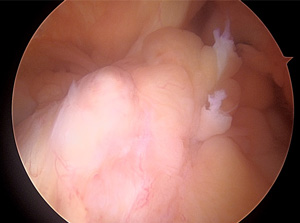

• 画像:再建した前十字靱帯(関節鏡)

再建した前十字靱帯(関節鏡)

• 画像:損傷後外側半月板関節鏡画像

損傷後外側半月板関節鏡画像

• 画像:部分切除後外側半月板関節鏡画像

部分切除後外側半月板関節鏡画像